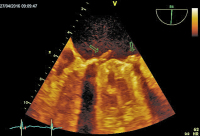

Vollbildansicht

Mitralklappenprothese - Chirurgenblick

Abbildung 3: Dreidimensionale Darstellung der Mitralklappenprothese in der sogenannten Chirurgenansicht. Mehrere Vegetationen am Klappenring (Pfeile)